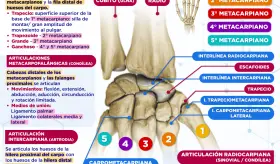

Un ensayo reciente compara dos tratamientos para la contractura de Dupuytren: la fasciectomía limitada y las inyecciones de colagenasa. Aunque las inyecciones son menos efectivas a largo plazo, su menor costo y recuperación más rápida las hacen atractivas para ciertos pacientes.